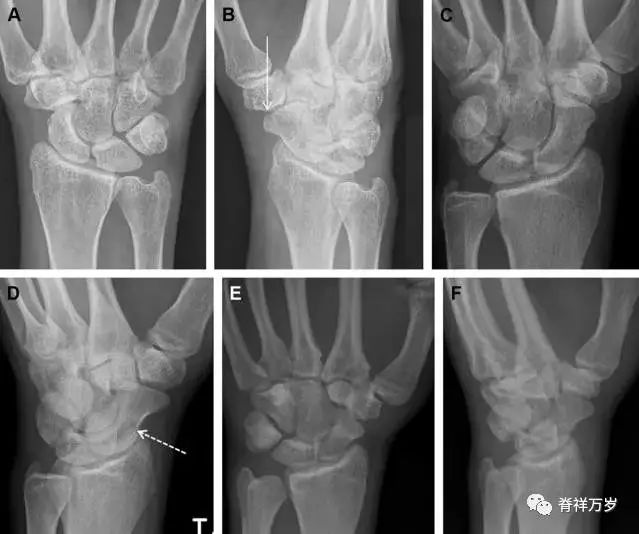

36.腕关节不稳定与脆弱区

月骨周围脱位和月骨周围骨折脱位常发生于摔倒后手掌撑地,由过伸、轴向*力暴**所致。所谓的「脆弱区」包括桡骨茎突、大多角骨、舟状骨、头状骨近端、钩状骨近端、三角骨的月骨缘、尺骨茎突。

图 7 经舟状骨骨折月骨周围脱位(腕关节前后位、斜位、侧位)。(A,B)前后位、斜位示月骨腰部骨折(黑箭头),第 1、2 腕弧中断,舟状骨近极(*)仍在原位,而远极(虚线)背侧脱位。